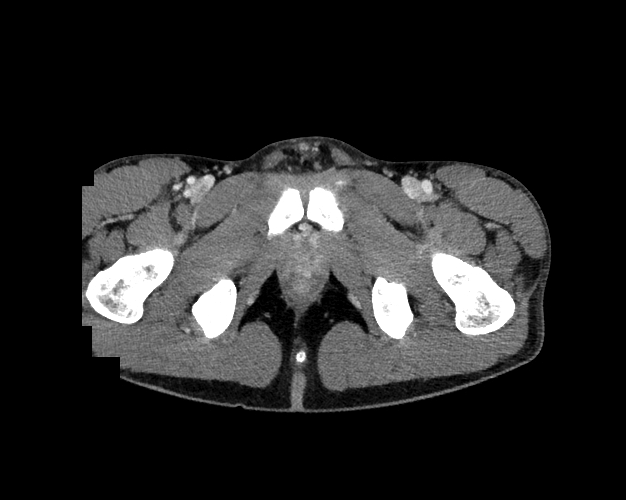

Body

Covers abdominal CT anatomy.